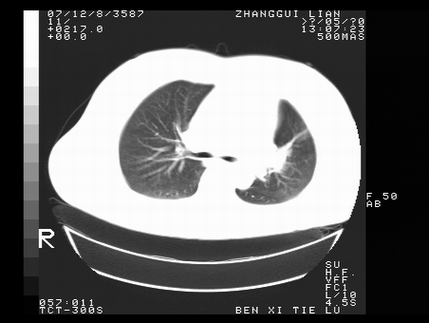

标题: CT10817:女,46,胸疼,无其他病史 [打印本页]

标题: CT10817:女,46,胸疼,无其他病史

左侧上纵隔旁团块影,部分植入纵隔,与纵隔界限不清,另:左肺门明显见团块,气管隆突前方见肿大淋巴结。考虑:左上肺纵隔型肺癌伴左肺门及纵隔淋巴结转移!

首先考虑左侧中央型肺癌伴阻塞性肺炎、纵隔内、弓旁淋巴结转移可能性大(纵隔窗调的欠佳)

1左上肺中心型肺癌伴左肺上叶不张2主动脉弓旁淋巴结转移3左下肺炎症

1 左侧中央型肺癌伴阻塞性肺炎 2 左肺门及纵隔淋巴结转移!3两侧胸腔及心包积液.

左侧胸廓塌陷,纵隔向左侧移位,左上肺不张。